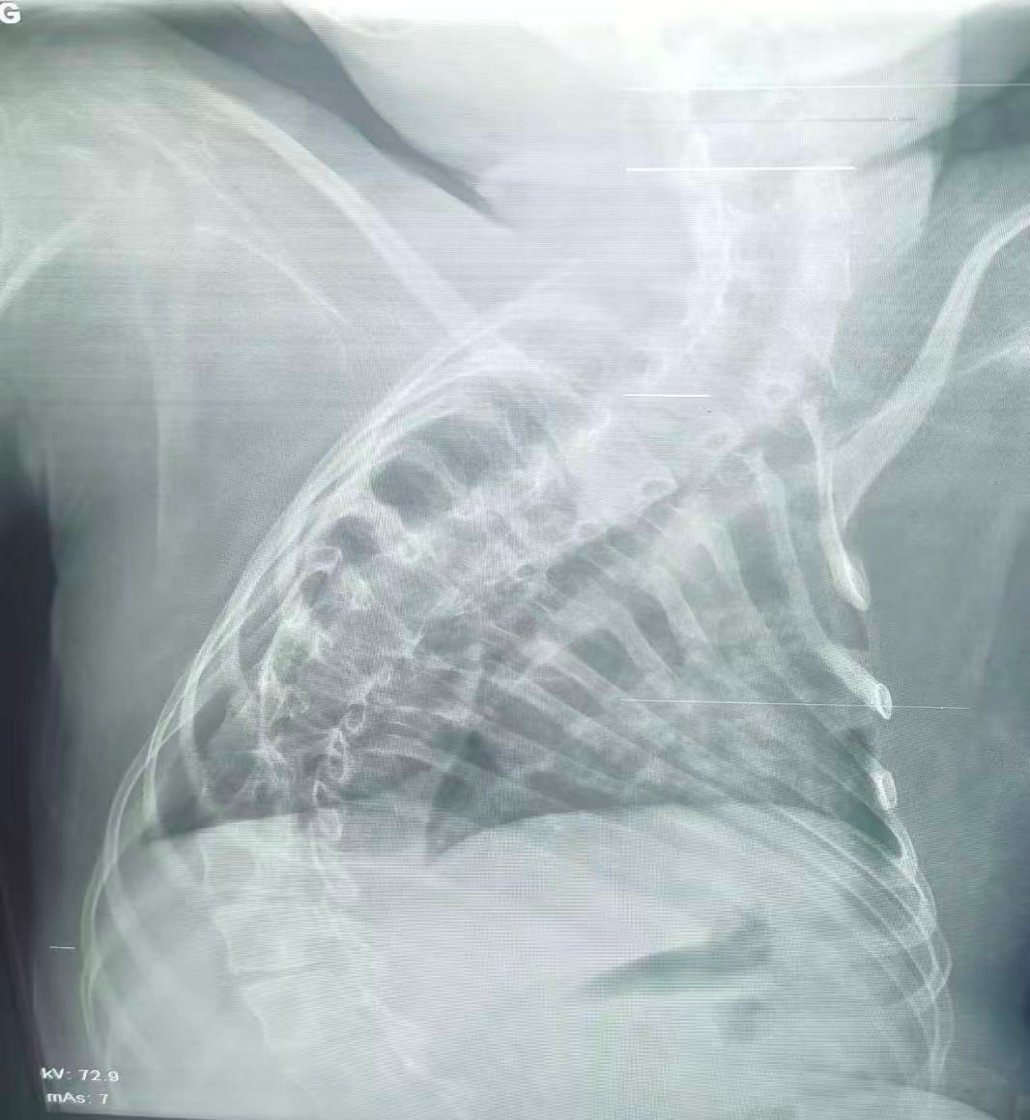

该患儿因患脊髓性肌萎缩症长期卧床,呼吸肌已严重无力,自主呼吸微弱且几乎丧失咳嗽排痰能力,此次并发支气管肺炎后,肺部感染迅速加重,生命已然悬于一线。更棘手的是,严重的脊柱侧弯使患儿胸廓畸形、气道解剖结构明显移位,常规纤支镜进镜路径完全失效,扭曲狭窄的气道如同纵横交错的“迷宫”,每一步操作都必须精准到毫米级别。

治疗前